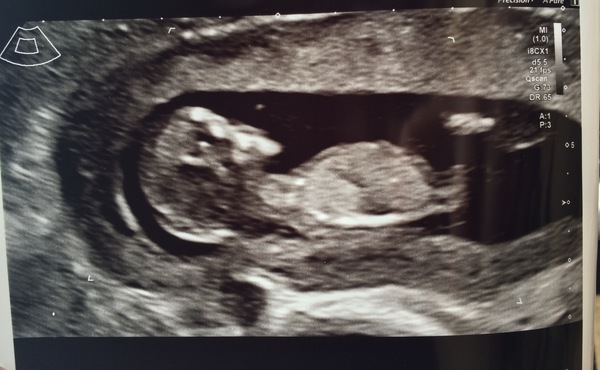

MonaTheMoaner · 01/03/2018 20:17

Anyone adept at the nub theory guess on this?

@Jfw82 I'd say girl based on the nub and tiny light.